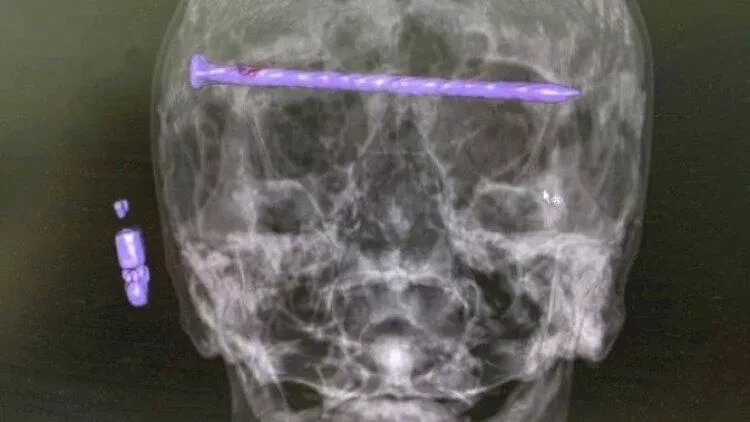

1 saylı şəhər xəstəxanasının neyrocərrahları ağır kəllə-beyin travması alan 78 yaşlı kişini əməliyyat ediblər. Məlumata görə, xəstənin həyatı xilas olunmaqla yanaşı, onun görmə qabiliyyəti qorunub.

"Xəstənin kəlləsində 15 santimetr uzunluğunda bir mismar var idi. O, göz yuvalarından və gicgahdan keçirdi", - deyə həkimlər bildiriblər.

Əməliyyat olunan təqaüdçü hazırda həkimlərin nəzarətindədir. Onun antibiotik terapiyasından sonra evə buraxılacağı açıqlanıb.